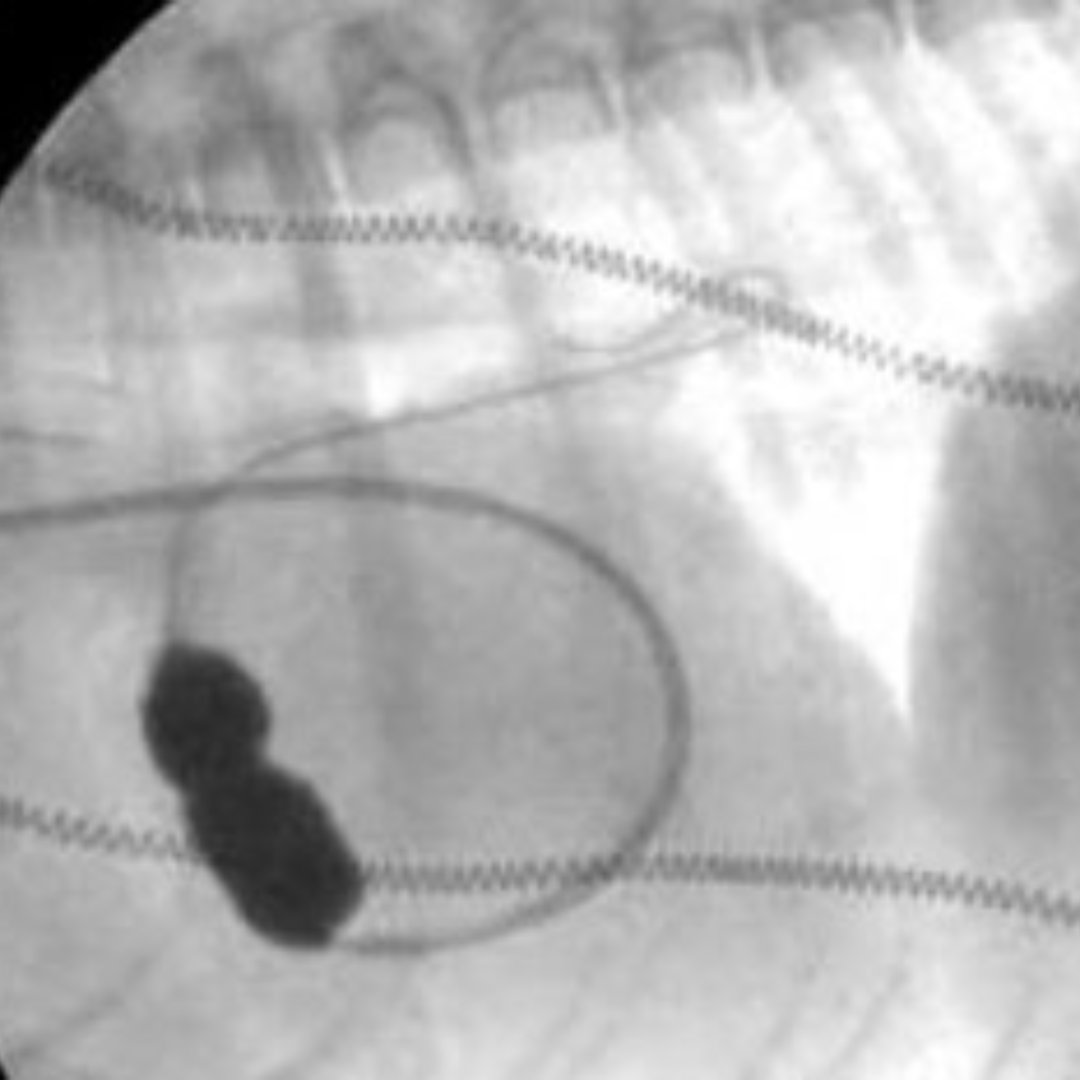

PDA Occlusion

Pulmonic Balloon Valvuloplasty & Stenting

Aortic Balloon Valvuloplasty